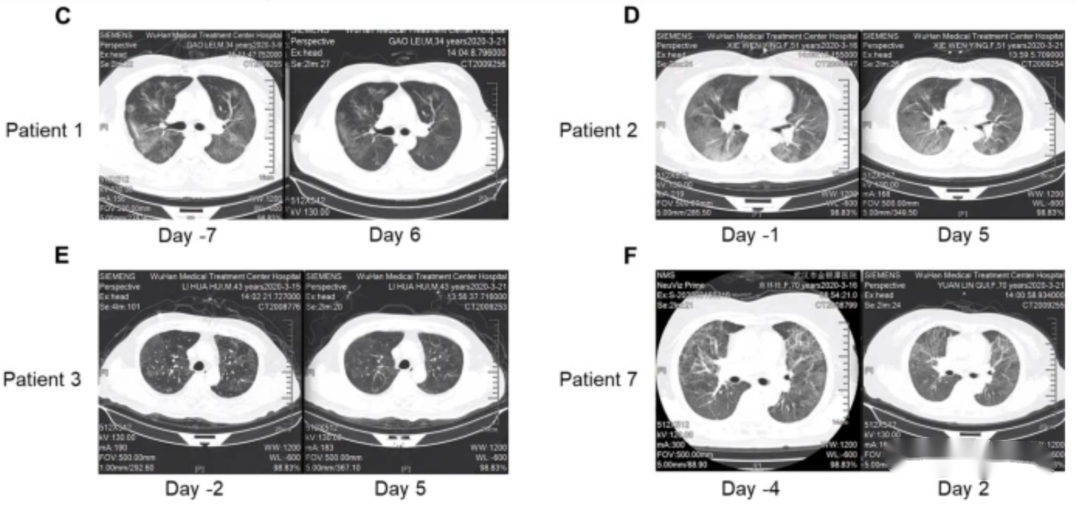

所有患者在气溶胶吸入haMSC-Exos后肺部病变不同程度的消退。下图C-E显示了患者1、患者2、患者3和患者7 气溶胶吸入haMSC-Exos前后的代表性胸部CT图像。患者7是一名70岁女性,在症状出现 (dso) 后38天住院,自47 dso 起接受气雾剂治疗,肺部影像改善最为明显(图E)。与43 dso 的结果相比,48 dso的CT图像上大量浸润和磨玻璃影消失。

COVID-19 患者吸入haMSC-Exos前后胸部 CT 扫描的变化